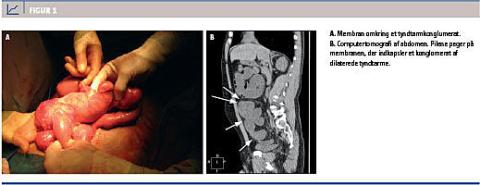

Den efterfølgende operation blev indledt laparoskopisk, men måtte konverteres til åben operation pga. manglende overblik over anatomien. Den proksimale halvdel af ileum og et mindre ileumkonglomerat analt herfor blev fundet indlejret i sækformede membranøse fortykkelser med dilateret tyndtarm oralt herfor (Figur 1A).

Diagnosen abdominal cocoon stilles sjældent præoperativt. Klinisk kan et asymmetrisk distenderet abdomen eller en palpabel udfyldning evt. erkendes. Ved CT af abdomen vil en sækformet membranøs fortykkelse omkring dilaterede tyndtarmsslynger være karakteristisk [4], hvilket også var tilfældet i denne sygehistorie (Figur 1B). Mesenteriel torsion, streng, adhærencer og intern herniering er blandt de radiologiske differentialdiagnostiske overvejelser. Det histologiske billede er præget af inflammation og fibrose [5].